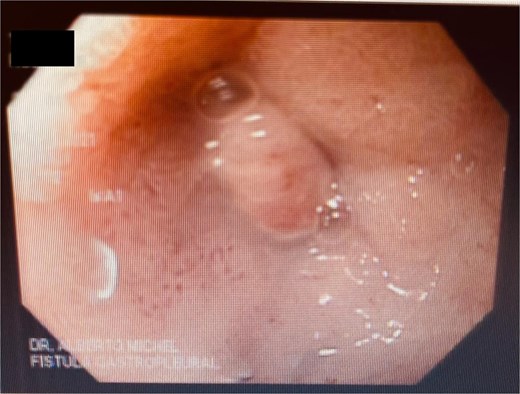

At the last endoscopy 30 days later, 100% granulation tissue was observed with no evidence of a fistulous orifice (Fig. 3). A leak test by fluoroscopy showed no leakage, allowing the initiation of a liquid diet for 15 days, progressing to a normal diet after one month. Follow-up endoscopy showed no pathological findings.

After follow-ups and sponge replacements, the closure of the fistulous defect can be observed.